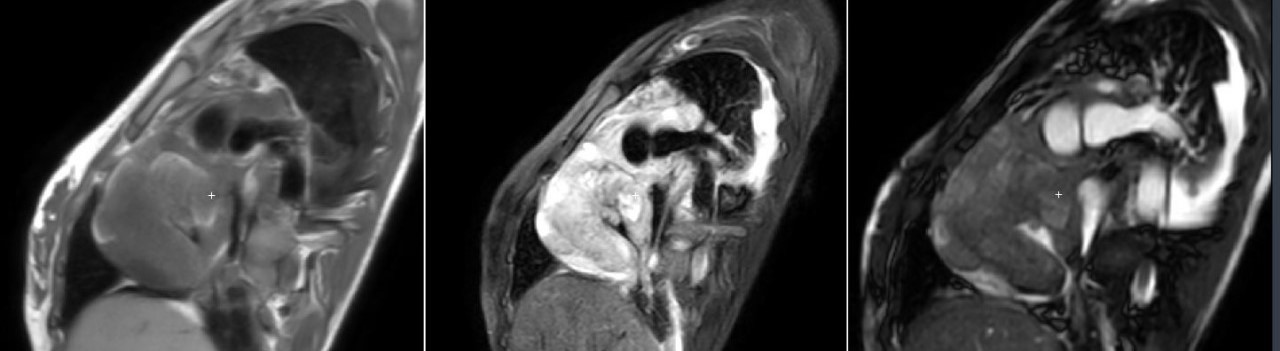

Image 2: Left: PSIR sequence 10 minutes after contrast injection in four chambers view showing heterogeneous enhancement with a central area of null signal suggesting avascular region. Right: 4 chambers BSSFP cine sequence showing typical cauliflower-like appearance plus residual pericardial and pleural effusion..jpg)